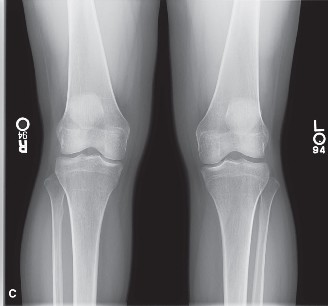

Standard radiographic evaluation of the knee is the first-line imaging modality for anterior knee pain. The patient's initial X-rays (Figures 9-1 A-C) include a weight-bearing anteroposterior (AP), a true lateral at 30 degrees of flexion, and an axial (Merchant or Sunrise) view.

The AP view demonstrates normal tibiofemoral joint spaces with no evidence of osteochondral lesions, loose bodies, or degenerative changes. The lateral view is scrutinized for patellar height. The Insall-Salvati ratio (the ratio of the patellar tendon length to the greatest diagonal length of the patella) is calculated at 1.05, which falls within the normal range (0.8 to 1.2), ruling out patella alta or baja. The lateral view also shows no evidence of trochlear dysplasia; the crossing sign is absent, and the trochlear bump is not prominent.

The Merchant view is arguably the most critical radiograph for this patient. It reveals a subtle lateral tilt of the patella and mild lateral subluxation. The sulcus angle measures 138 degrees (normal is typically <145 degrees), indicating adequate trochlear depth. However, the congruence angle is slightly lateralized, confirming the clinical suspicion of lateral patellar maltracking. There is no evidence of advanced patellofemoral osteoarthritis, osteophyte formation, or subchondral sclerosis.